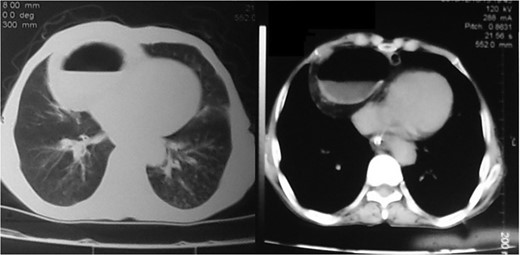

An 80-year-old man presented to our emergency room with multiple episodes of non-bilious vomiting for 4 days and not-passing stool or flatus for 2 days. He also complained of intermittent pain in the upper abdomen, which was not associated with fever, chest pain, melena or diarrhea in the recent past. However, he complained of increased cough and shortness of breath for the last 4 days on the background of a diagnosed chronic obstructive pulmonary disease. There were no similar complaints in the past. On examination, his vital parameters were normal, other than an oxygen saturation of 82% for which oxygen had to be given via face mask. His abdominal examination revealed epigastric fullness with tenderness in the epigastric and right hypochondrium. There was no evidence of peritonitis. Laboratory investigations revealed hypokalemia (3.1 mEq/l) with other parameters being normal. On the chest X-ray obtained, we saw air–fluid levels in the right thoracic cavity (Fig. 1). Computed tomography (CT) scan of the abdomen performed demonstrated a right anterior diaphragmatic hernia with stomach as content. (Figs 2 and 3) The patient was taken to the operating room, and an upper midline laparotomy was performed. Findings included an ~4 × 3 cm defect to the right of the sternum in the anterior diaphragm (Fig. 4), with incarcerated pylorus/antrum of stomach as contents and a grossly distended stomach. Rest of the bowel was normal. The contents were reduced, and the defect closed primarily with 2-0 non-absorbable interrupted mattress sutures (Fig. 5). Postoperative period was uneventful, and chest X-ray revealed a corrected defect with reduced contents (Fig. 6). The patient was started orally on the first postoperative day and discharged on the sixth postoperative day.

Diagnosis is usually suggested by chest X-rays indicating an air–fluid level in the chest with Barium studies revealing contrast in the stomach/bowel herniating through the diaphragm. CT scan of the chest and diaphragm are highly accurate and help proceed with surgical management [7].